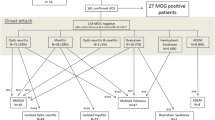

There is a wide variety of clinical-MRI phenotypes associated with MOGAD. The initially described patterns include ADEM, optic neuritis, and transverse myelitis. These can occur separately or in combination, altogether comprising more than 90% of pediatric MOGAD presentations [20,21,22]. Included are also children with neuromyelitis optica spectrum disorder-like phenotype that can present with simultaneous or sequential optic neuritis and transverse myelitis, and can exhibit other core features of neuromyelitis optica spectrum disorder such as brainstem syndrome. MOG antibodies are common in AQP4-IgG-seronegative neuromyelitis optica spectrum disorder, being reported in up to 83.4% of pediatric AQP4-IgG-seronegative patients [23, 24].

The MOGAD phenotype is age dependent, which might reflect variability in MOG expression at different age groups. Young children (<11 years) tend to present with ADEM phenotype, while older patients (≥11 years) present more commonly with optic neuritis [14, 20]. The severity of attacks and degree of recovery are also age dependent, with younger children presenting with worst clinical-radiological severity, but with faster and more complete recovery [6].

ADEM is an encephalopathy associated with multifocal neurologic deficits (motor deficits, seizures, and cerebellar symptoms), as defined by the IPMSSG [25]. Fifty percent of children presenting with a first ADEM attack will have MOG antibodies [8, 21]. In addition, almost all patients demonstrating a relapsing course of disease, namely multiphasic disseminated encephalomyelitis or ADEM followed by optic neuritis (ADEM-optic neuritis), will be MOG antibody seropositive [13, 32].

Clinical relapse

Most pediatric MOGAD presentations are monophasic; however, 20–30% of children may exhibit a relapsing disease [14, 16, 26, 80, 81]. The time to first relapse is commonly within 1 year and typically within 3 years; however, first relapse events were documented even more than 10 years after initial attack [81]. Younger children (<10 years) tend to present with severe disability at disease onset, but frequently demonstrate substantial recovery as compared to older patients, with lower relapse rate [14, 34]. Published data regarding risk factors for relapsing course is inconclusive. Several studies reported increased risk associated with persistent MOG antibody seropositivity or with high MOG antibody titers [26, 34]. Nevertheless, other publications did not observe such associations [69, 82], and relapse of disease occurred also in patients who converted to seronegativity [20]. No radiological features at onset have been associated with risk of relapse [69, 80], but worsening of imaging with new lesions appearing at first follow-up MRI is a predictor of relapse [11].

The clinical-MRI phenotype at relapse may differ from the phenotype at initial presentation, and different patterns may evolve during the disease course [81]. The most common variation is the development of optic neuritis at subsequent relapse. Other relapse patterns include multiphasic disseminated encephalomyelitis, ADEM-optic neuritis, transverse myelitis, neuromyelitis optica spectrum disorder-like phenotype, autoimmune encephalitis, leukoencephalopathy-like pattern, and other unclassified presentations [36, 81] (Fig. 17). In a single-center retrospective study of 61 children with MOGAD, age-related phenotype persisted into first relapse (but not into second relapse), with younger children (≤9 years) most commonly presenting with ADEM-like pattern (34.8%), and older children (>9 years) most commonly presenting with FLAMES at first relapse [69]. In a prospective multicenter study of 102 children with MOGAD, first relapse phenotype demonstrated age dependency, with multiphasic disseminated encephalomyelitis and ADEM-optic neuritis more prevalent in children ≤9 years (Fig. 17), and recurrent optic neuritis and neuromyelitis optica spectrum disorder-like phenotype more prevalent in children older than 9 years [83].